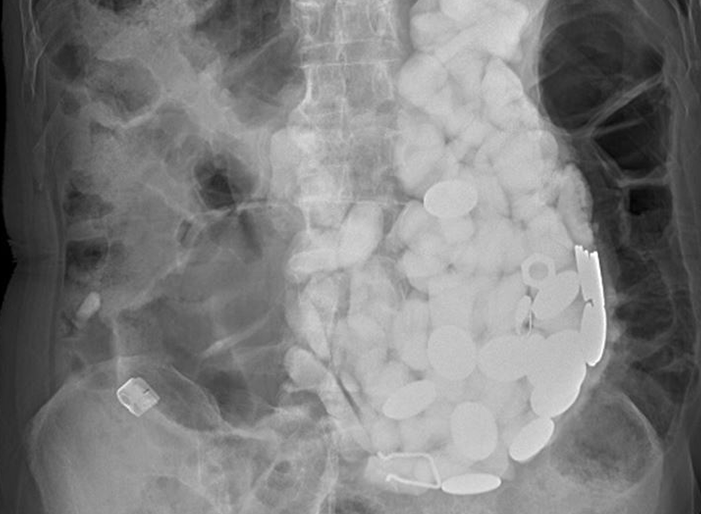

Sau khi chụp x-quang, bác sĩ nhận thấy có dị vật lớn, chiếm toàn bộ dạ dày của người bệnh.

Một khối lượng đá, nắp chai và đồng xu đã lấp kín dạ dày của nam bệnh nhân. (Ảnh: The Sun)

Cách này không mang lại hiệu quả bởi có quá nhiều dị vật bên trong dạ dày người đàn ông cần được loại bỏ. Các bác sĩ quyết định phẫu thuật, gắp từng dị vật ra. Lúc này mới hoảng hồn khi đó đều là đá cuội, tiền xu và nắp chai.